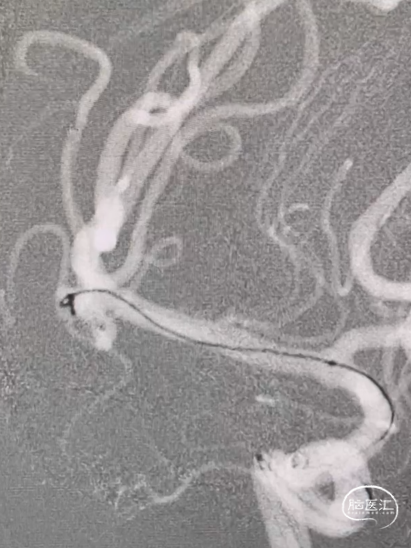

释放支架后,再依次送入2*3mm、1.5*2mm两枚弹簧圈完成治疗。

术后造影显示各分支血管通畅,动脉瘤不再显影。